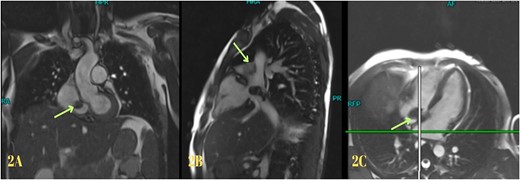

Blood investigations revealed leukocytosis and thrombocytopenia (Table 1). His electrocardiogram (ECG) showed a normal sinus rhythm, and chest X-ray revealed bilateral infiltrates. A high-resolution computed tomography (HRCT) scan of the chest was done in February 2020, which showed multiple patchy pulmonary infiltrates in the upper and lower lobe of the left lung, the middle lobe and the lower lobe of the right lung (Fig. 1). An air bronchogram was noted within the area of consolidation of the middle lobe of the right lung. Also, heavy calcification of irregular areas within the right atrium, extending up to the opening of the IVC, was noted. We did a further investigation with transthoracic echocardiography, which revealed an echogenic mass in the right atrium of 3.0 ✕ 1.9 cm2, most likely a thrombus. Following this, we investigated the patient with cardiac MRI, which showed a large irregular mass of 25 ✕ 18 mm2 in the right atrium attached to the interatrial septum and extending to the IVC, most likely myxoma with superimposed thrombus (Fig. 2).

(A and B) Axial and coronal views of a high-resolution computed tomography scan of the chest showing multiple opacifications in the lung field and heavy calcification within the right atrium, extending up to the opening of the inferior vena cava.